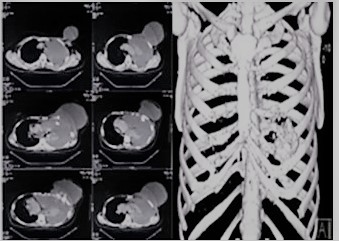

Entre los estudios de imágenes que se realiza, muestra una de RX tórax simple AP-L de 2019, donde se observa derrame pleural izquierdo con desplazamiento del cardiomediastino a la derecha (Figura 1B). Una RX de tórax PA de 2012 donde se evidencia cambios en la densidad ósea del 5o arco costal anterior izquierdo con pérdida de la cortical y TAC de tórax con contraste del mismo año en la cual se identifica un tumor de 4 cm x 5 cm en el 5o arco costal, de bordes definidos, de crecimiento expansivo con línea fina de cortical residual de la costilla sin signos de extensión a tejidos blandos, tórax o mama (Figura 2). En abril de 2019 realiza tomografía de tórax (Figura 3) con contraste y reconstrucción en 3D, donde se observa una lesión de 30 cm x 20 cm, que compromete 4o 5o y 6o arco costal anterior, expansiva, lítica, bordes mal definidos con destrucción de la cortical, desplazando pulmón izquierdo y mediastino sin infiltrarlos, compromete la totalidad de la mama izquierda, en relación íntima con el pericardio desplazándolo a línea media y derrame pleural izquierdo masivo.